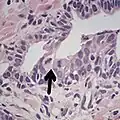

Intraductal carcinoma of the prostate with an infiltrative growth pattern may be morphologically difficult to distinguish from invasive cancer. One focus shows comedonecrosis (arrow), morphologically suggesting Gleason pattern 5 invasive carcinoma (a haematoxylin and eosin, b CK5/6)[19]

Intraductal carcinoma of the prostate with very patchy basal cells identified by immunohistochemistry. At least some of the glands lacking basal cell immunoreactivity represent intraductal rather than invasive carcinoma (a haematoxylin and eosin, b CK 5/6)[19]